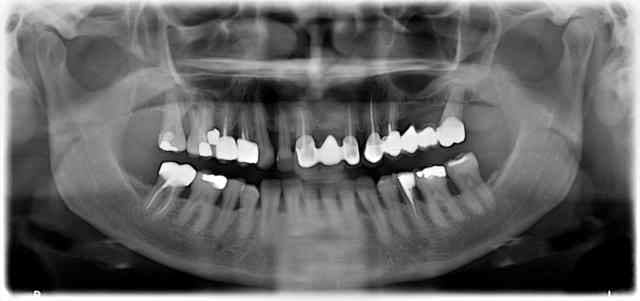

Vue l'état du tenon sur la 24 et le niveau d'os sur 27 le bridge secteur 2 risque de pas durer longtemps.

Couronne sur 35 avant que la carie passe sous l'os.

La 16, 15 et 14 carie sous gingival.

Voir pour une solution durable au maxillaire. Peut etre courrone pour stabiliser un amovible ou bridge complet avec ou sans implant. Mais refaire juste les trois dents anterieur c'est du court terme et ça va limiter les options pour refaire les secteurs postérieures.

All-on-8/10 en haut...ou complet...sérieusement tout est moche la haut.

Pas d'implant en avant avec le reste dans cet état...

Pour ma part, je ne suis pas capable de faire un pronostic sur la pano même si en effet le bridge secteur 2 semble promis à un sombre avenir et la 26 m'inquiète. Le reste; je me méfie des panoramiques .....

Pas faux (fracture céramique sur 23 aussi: il y'a quelque chose qui déconne dans l'occlusion de cette reconstruction).

Le problème ici c'est que quasiment toutes les dents du haut sont presque en décompensation (pb paro, carie racinaire, tenon hors axe) pour l’instant ça tiend mais pour combien de temps. Et une fois qu'un élément va tomber, pour refaire du fixe sur c'est piliers, c'est pas gagnè

Mettre un implant : ok, on va ajouter un élément osteointégré a une structure prothétique qui ne l'est pas, normalement ça se règle avec l'occlusion, mais ça sous entend que le reste des éléments dentaire est relativement stable (pas de carie de racine, d’atteinte de la furcation, ect ) ici c'est loin d’être le cas.